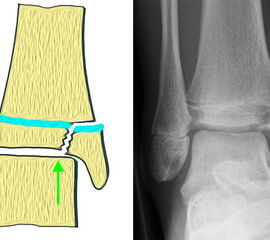

Bei den medialen Malleolarfrakturen handelt es sich um Fugengelenkfrakturen bzw. Aitken II und III Verletzungen. Kennzeichnend ist, dass der Frakturverlauf die wachstumsaktive Zone zur Epiphyse hin durchkreuzt. Die Verletzung der wachstumsaktiven Zone macht diese Verletzungen besonders problematisch.

Fugengelenkfrakturen treten typischerweise vor dem 10. Lebensjahr auf, in einer Phase, in welcher die Wachstumsfugen noch weit offen sind. Dieser Frakturtyp betrifft fast ausschließlich den medialen Malleolus. Laterale Frakturen sind extrem selten, teilweise kommt es zu lateralen Bandverletzungen oder Fugenschaftfrakturen der distalen Fibula. Die Frakturlinie verläuft in einer Verlängerungslinie von der medialen Taluskante nach proximal. Häufig stellen sich Verletzungen des Innenknöchels im Röntgenbild schlechter dar, insbesondere wenn die Aufnahmen verdreht sind oder die Ebene der Fraktur bei geringer Dislokation verkippt zur Röntgenebene liegt. Besteht klinisch der geringste Hinweis auf eine Verletzung des Innenknöchels, muss aufgrund der Tragweite der Verletzung durch entsprechende Aufnahmen gegebenenfalls auch Schnittbildverfahren die Verletzung sicher diagnostiziert oder ausgeschlossen werden (Abb. 15).

Fugengelenkfrakturen können die Wachstumsfuge durchkreuzen (Abbildung 16a), ohne oder nur mit minimaler Beteiligung der Fuge sehr weit medial liegen (Abbildung 16b) oder durch die Fuge auslaufen (Abbildung 16c). Relevant für die Wachstumsprognose ist weniger die Form der Fraktur, sondern das Alter des Patienten zum Zeitpunkt des Traumas sowie das Ausmaß der Schädigung der Wachstumsfuge, wobei eine Korrelation mit dem Ausmaß der Dislokation besteht.